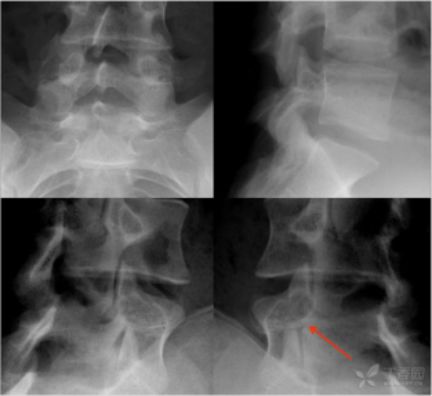

1、X线:部位、类型、程度;(正侧位、双斜位、动力位、颈椎张口位等)

2、CT:可显示椎体的骨折情况,可显示有无碎骨片突出于椎管内,计算椎管前后径损失了多少,不能显示脊髓受损情况。(平扫、薄扫、三维、表面重建等)

(1)压缩骨折

为临床最常见的一种类型,椎体前方受压缩楔形变。压缩程度以椎体前缘高度占后缘高度的比值计算。分度为前缘高度与后缘高度之比,Ⅰ°为1/3,Ⅱ°为1/2,Ⅲ°为2/3。

椎体压缩骨折的一种特殊形式,椎体呈粉碎骨折,骨折块向四周移位,向后移位可压迫脊髓、神经,椎体前后径和横径均增加,两侧椎弓根距离加宽,椎体高度减小。